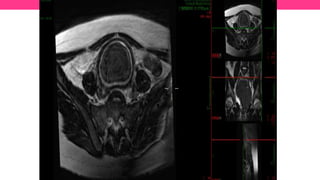

Fig. 4: Fig. 4: Síndrome de Mayer-Rokitansky-Küster-Hauser. A . Sagital FSE T2. B y C. Axial FSE T2. D. FSE T2

con supresión de grasa . La RM muestra la ausencia de útero y vagina. La uretra (flecha blanca sólida) está

situada inmediatamente anterior a la pared rectal (flecha blanca transparente). Agenesia renal izquierda (triángulo

blanco sólido).

Fig. 4: Fig.4: Síndrome de Mayer-Rokitansky-Küster-Hauser. A . Sagital FSE T2. B y C. Axial FSE T2. D. FSE T2 con supresión de grasa . La RM muestra la ausencia de útero y vagina. La uretra (flecha blanca sólida) está situada inmediatamente anterior a la pared rectal (flecha blanca transparente). Agenesia renal izquierda (triángulo blanco sólido).